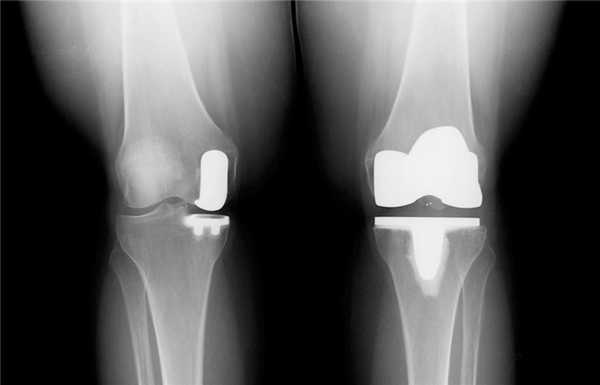

Посмотрите на рентген, на нем вы видите, до какой степени при запущенном гонартрозе изношен гиалиновый хрящ, обеспечивающий гладкое скольжение суставных поверхностей. Концевые участки костей грубо деформируются нарушая функции сгибания и разгибания конечности вызывая интенсивный болевой синдром.

Сравнение здорового и пораженного сустава.